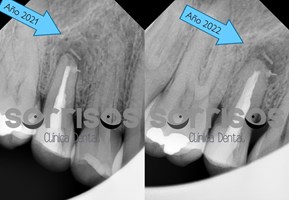

Paciente que acude con ligera molestia a percusión y palpación en 2021. Se observa tratamiento de conductos con sellado incompleto y lesión radiolúcida (oscura) en el contorno de la raíz. Se explica que puede ser necesario el retratamiento con apicectomía. Prefiere esperar y seguimos reevaluando periódicamente.

En 2024 la lesión aumenta de tamaño y clínicamente se aprecia a través de la encía una fístula que comunica con el diente.